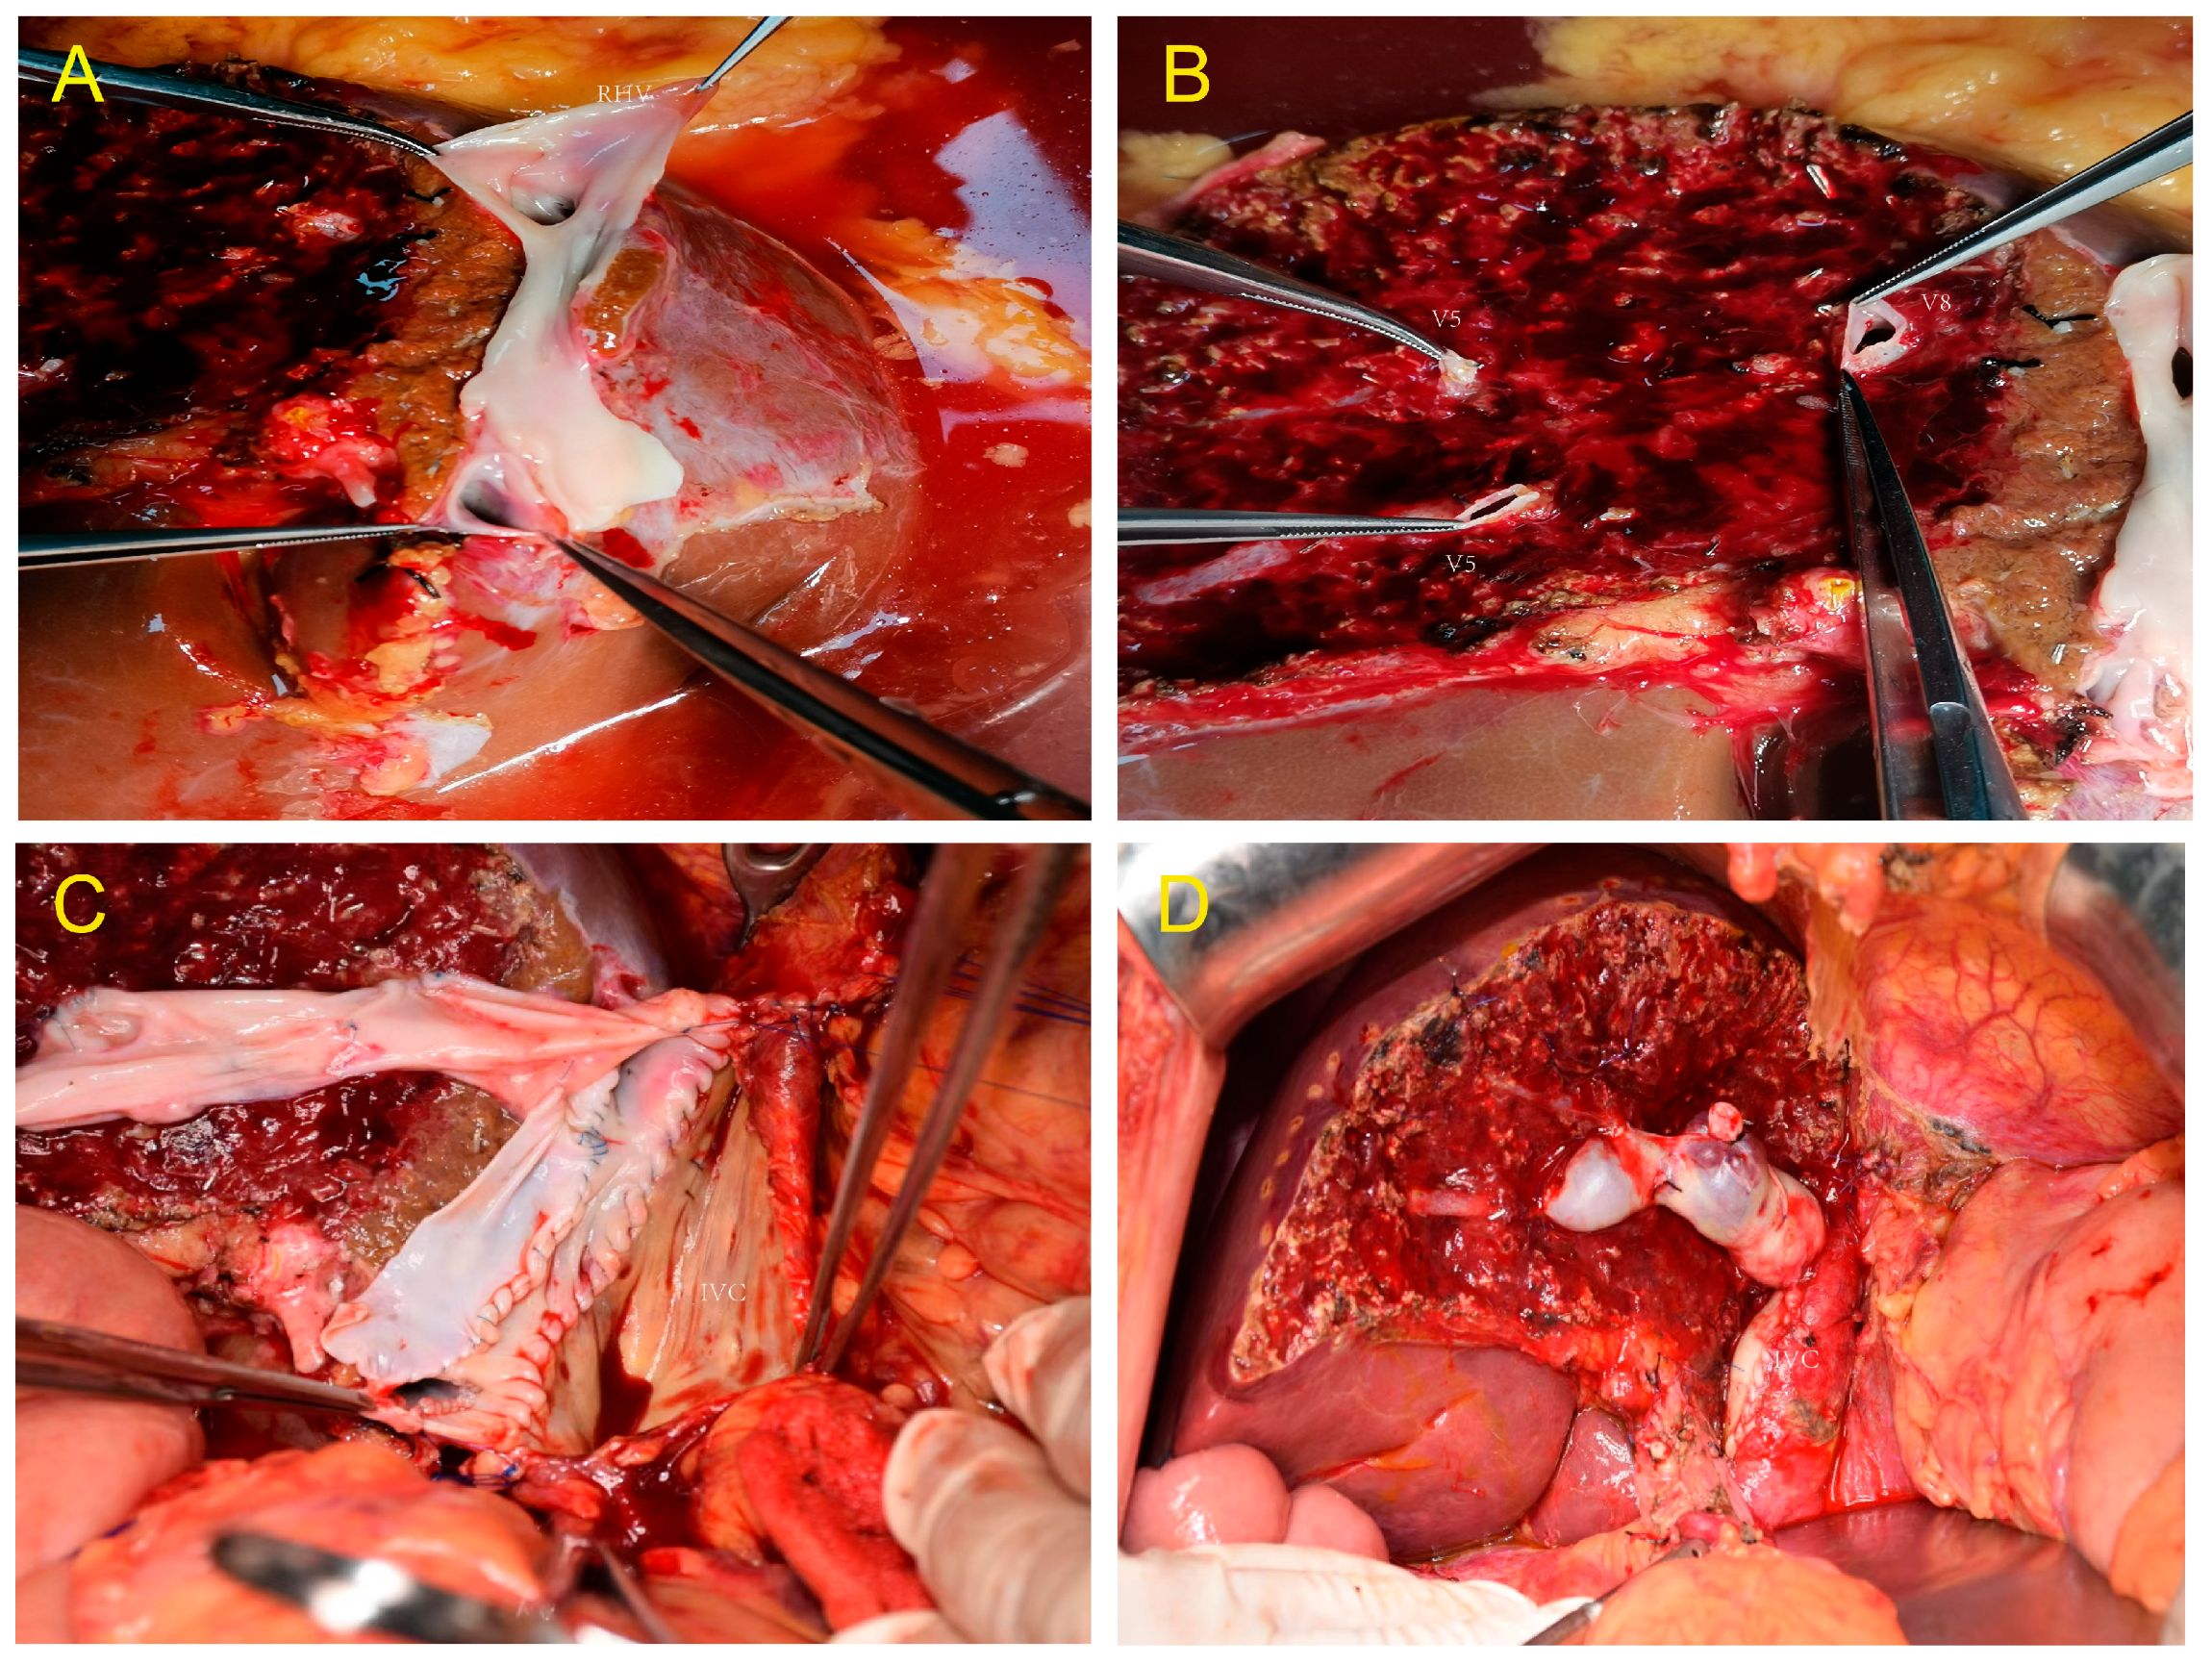

2.4. Donor Liver Harvest—Splitting Technique

2.5. Recipient Surgery